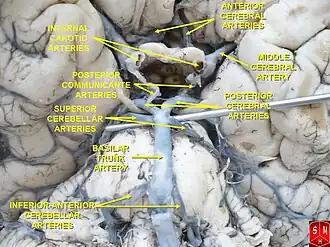

Медиальная поверхность больших полушарий головного мозга, показывающая области, кровоснабжаемые теми или иными мозговыми артериями. Области, кровоснабжаемые задней мозговой артерией, показаны жёлтым цветом. Артерии головного мозга, вид со стороны основания мозга (снизу). Задняя мозговая артерия, составляющая часть Виллизиева круга, отмечена вблизи центра изображения. С правой стороны удалена часть височной доли коры больших полушарий головного мозга, а также часть правого полушария мозжечка.

Артерии головного мозга, вид со стороны основания мозга (снизу). Задняя мозговая артерия, составляющая часть Виллизиева круга, отмечена вблизи центра изображения. С правой стороны удалена часть височной доли коры больших полушарий головного мозга, а также часть правого полушария мозжечка.